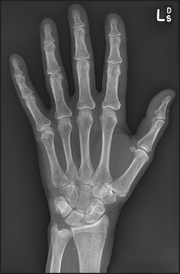

The articulations between the phalanges are synovial hinge joints. The eight bones of the wrist (carpal bones) form gliding joints that allow wrist movements—flexion/extension and abduction/adduction as they slide over each other.

Figure 24.3 X-ray of normal hand (Courtesy M Thomson, National Capital Diagnostic Imaging, Canberra.)